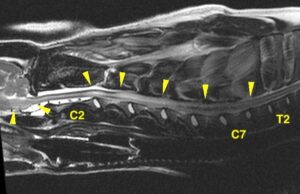

*頚髄のほぼ全域が異常に白く認められた

臨床症状とも合わせ、出血を伴う脳脊髄の壊死を疑う

*首を走っている太い神経